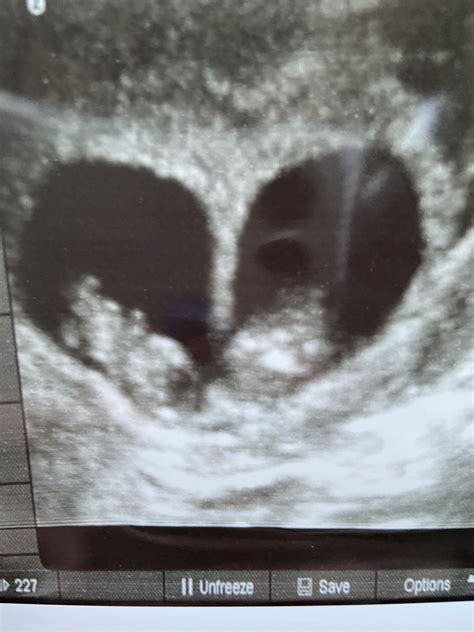

The Ultrasound 9 Weeks Twins scan is typically performed between 8 and 10 weeks of pregnancy. At this stage, the embryos are still very small, but significant developments are occurring. The primary goal of this ultrasound is to confirm the presence of two gestational sacs, each containing an embryo. This confirmation is crucial for determining the type of twin pregnancy—whether it is dizygotic (fraternal) or monozygotic (identical).

During the Ultrasound 9 Weeks Twins scan, the ultrasound technician will use a transvaginal probe to get a clear view of the uterus. This method provides a more detailed image compared to the transabdominal approach, especially at this early stage. The procedure is generally painless, although some women may experience slight discomfort. The technician will measure the size of each embryo and check for a heartbeat, which is usually detectable by this week.

• Confirmation of two gestational sacs.

• Measurement of the crown-rump length (CRL) of each embryo.

• Detection of fetal heartbeats.